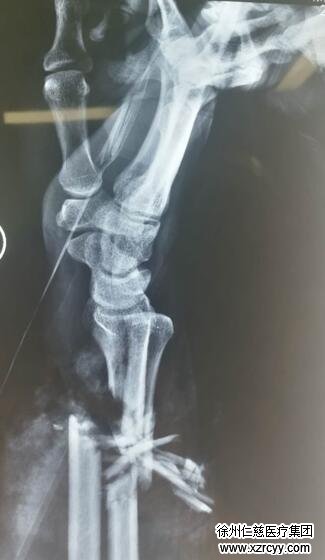

23:00,付锡被送到必威官方首页官网betway。值班的手外三李刚医生接诊,付师傅疼得脸发青,一旁的工友抢着几句话讲明了病因。李医生立即展开检查,伤者右前臂中段离段,前臂近端肢体肿胀明显,离断肢体冷瘪,满布瘀斑,苍白无血运。又安排CT检查,诊断为创伤性前臂切断。

手术准备迅速进行,明亮的灯光下,李刚医生争分夺秒,为伤者实施“右前臂清创再植术”,麻醉后,首先彻底清除伤者右前臂坏死、失活的组织,止血,仔细清创伤处碎裂的骨质,光清理出来的碎骨质就有一小盆。然后,复位尺桡骨骨折断端,外固定支架固定,接通尺桡动脉通血,依次修复断裂的肌腱、肌肉及神经,术中输血2000毫升。观察右手肢体颜色红润,温度、张力正常,毛细血管反应灵敏,手术获得了成功。